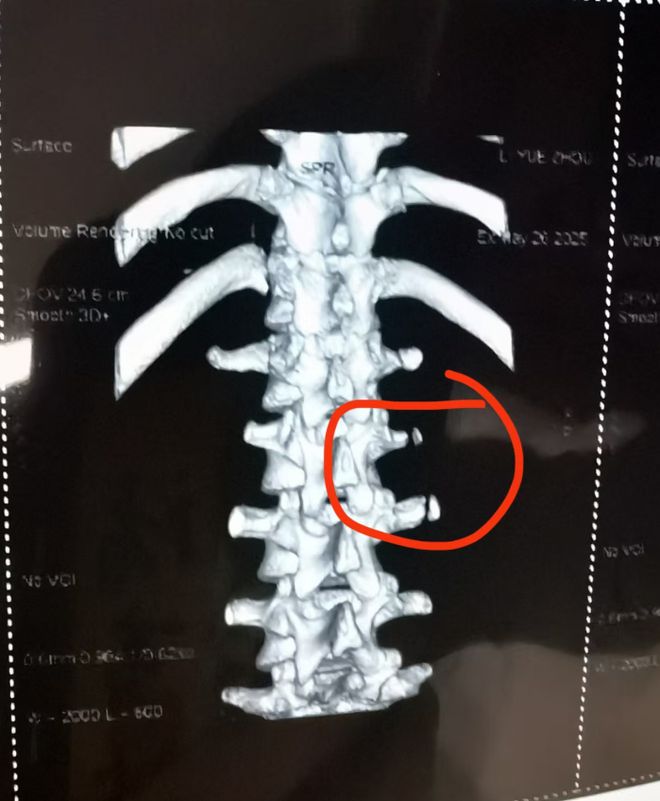

6月9日,浙江男篮公布了国青球员李悦洲的伤病情况,他因为在训练中横突骨折,将会缺席三个月。

但无论浙江方面还是曲绍斌,都没有说李悦洲到底是怎么受伤的,坊间有传闻,是训练场边堆有杂物,另外还有一种说法是场边的广告牌,导致李悦洲骨折。